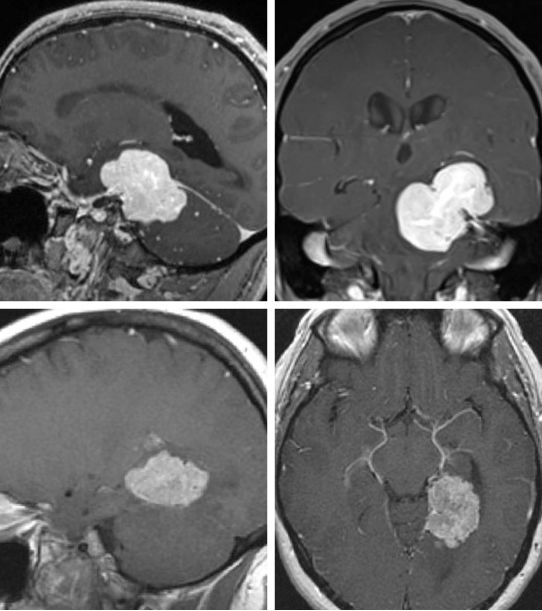

图2. 松果体区(左图)及中脑后外侧(右图)大型病变可以很容易通过小脑上入路显露。